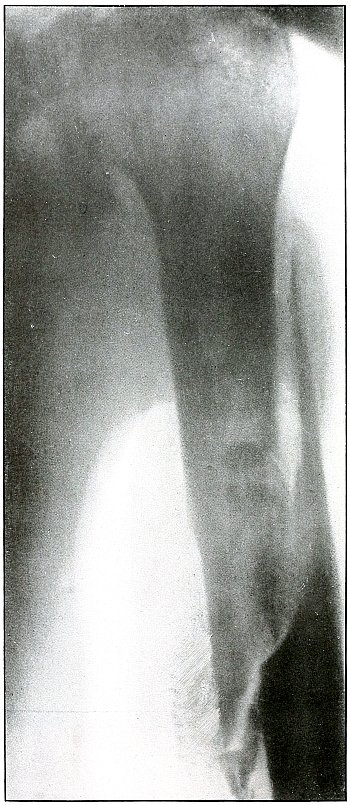

48. Gunshot wound, thigh 106

49. Gunshot wound, thigh 108

50. Gunshot wound, thigh 110